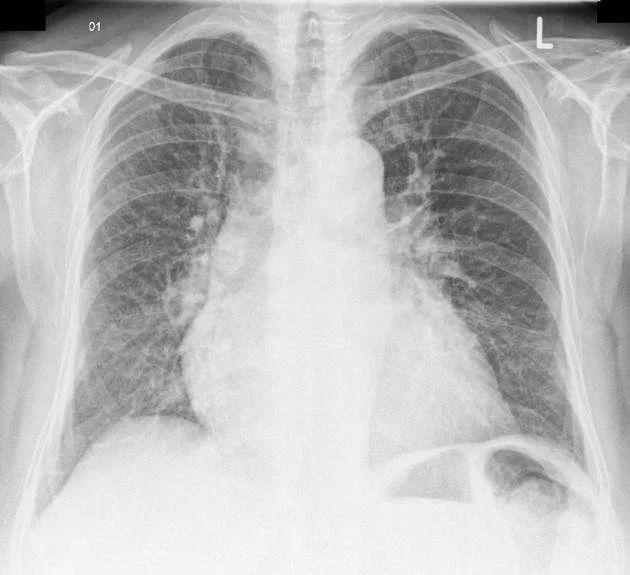

Frontal chest xray shows enlarged heart and patchy shadows in the lungs due to heart failure

For example, heart failure can cause worsening of shortness of breath due to backup of fluid into the lungs due to impaired pumping function of the heart. Generally, heart failure can occur in 20% of individuals with COPD due to overlapping risk factors (aging and history of cigarette smoking). An irregular heart rhythm, such as atrial fibrillation, can cause shortness of breath without necessarily leading to heart failure. Additional symptoms may include atypical chest discomfort, palpitations, and lightheadedness.

Testing depends on possible causes being considered by the health care professional. Checking your vital signs (heart rate and blood pressure) along with measuring your oxygen saturation are essential first steps in the evaluation. A chest xray is commonly ordered because it can usually confirm the presence of heart failure (see image above), pneumonia. pneumothorax, and pleural effusion along with other possibilities. An electrocardiogram (ECG) may be ordered if it is supected that you have had a heart attack (along with blood tests) or to evaluate for possible irregular heart rhythm.